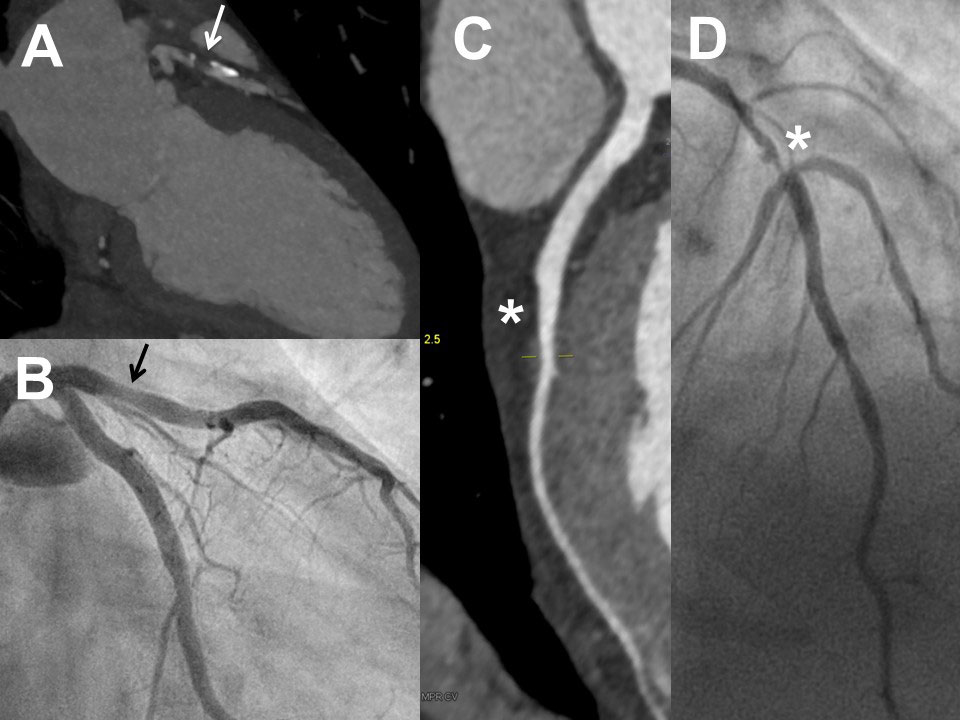

As shown in table 2 and figure 1, not all patients undergoing invasive coronary angiography had coronary artery disease by CCTA. However, invasive coronary angiography identified coronary artery disease in a high proportion of patients in all pretest probability groups (between 67 and 88%): there were 47 patients with coronary artery disease by invasive coronary angiography, 36 of whom underwent revascularisation. Notably, there were 14 patients with pretest probability <15% in whom invasive coronary angiography demonstrated coronary artery disease and nine out of these 14 patients underwent coronary revascularisation. Detailed findings of CCTA and invasive coronary angiography in the 59 patients who underwent both tests are shown in supplementary table S1 in appendix 1. In figures 2 and 3 , some representative examples of CCTA and invasive coronary angiography are shown.

Figure 3 Examples of coronary computed tomography (CCTA) and invasive coronary angiography (ICA) in two patients with non-optimal correlation of the two methods: Frist patient (female, 54 years) with severe stenosis of the proximal left anterior descending artery in CCTA (panel A, arrow) but eccentric plaque without significant stenosis in ICA (panel B, arrow; lesion looking less relevant in other projections, absolutely normal fractional flow reserve). Second patient (female, 61 years) with no significant stenosis of the mid left anterior descending artery in CCTA (panel C, asterisk) but severe stenosis of the mid left anterior descending artery in ICA (panel D, asterisk).